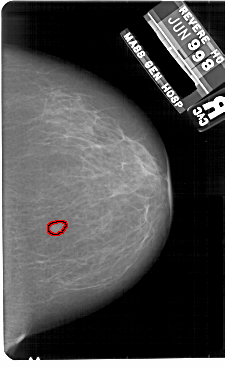

A_1816_1.RIGHT_MLO

RIGHT_CC LINES 5491 PIXELS_PER_LINE 3361 BITS_PER_PIXEL 12 RESOLUTION 43.5 OVERLAY

FILE: A_1816_1.RIGHT_CC.OVERLAY

TOTAL_ABNORMALITIES 1

ABNORMALITY 1

LESION_TYPE MASS SHAPE IRREGULAR MARGINS ILL_DEFINED

LESION_TYPE CALCIFICATION TYPE PUNCTATE DISTRIBUTION CLUSTERED

ASSESSMENT 4

SUBTLETY 2

PATHOLOGY MALIGNANT

TOTAL_OUTLINES 1

BOUNDARY